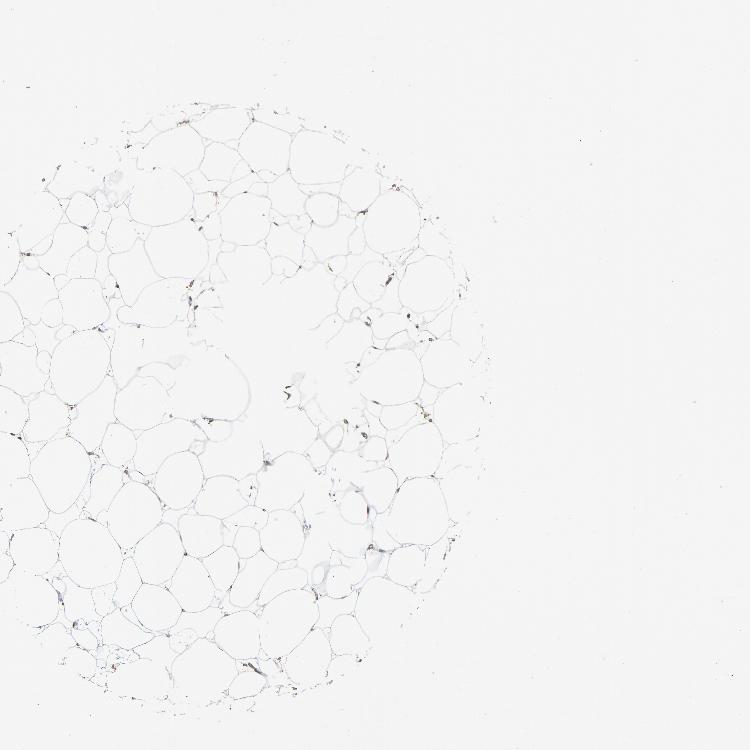

SOFT TISSUE 1 - Antibody stainingi

Antibody staining in the annotated cell types in the current human tissue is reported as not detected, low, medium, or high, based on conventional immunohistochemistry profiling in selected tissues. This score is based on the combination of the staining intensity and fraction of stained cells.

Each image is clickable and will lead to virtual microscopy that enables deeper exploration of all samples and also displays staining intensity scores, fraction scores and subcellular localization as well as patient and tissue information for each sample.

Antibody HPA001923Antibody HPA003908

Fibroblasts Not detectedNot detected